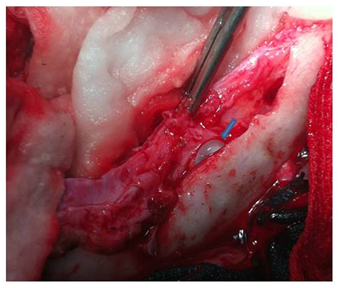

An eight-year-old girl underwent surgery for the removal of an intracerebral frontal left hydatid cyst three years ago. She didn’t take any regular medical therapy following surgery. She came with intermittent headaches and vomiting for two months. There was no history of recent trauma. Physical examination revealed a healthy child in no distress. There was no frontal syndrome. Chest X rays and abdomen ultrasonography were normal. CT scan revealed a relatively large left frontal cystic lesion of similar density to cerebro-spinal fluid, with another small separate one in the epidural space in the adjacent region close to the midline, associated to bone exostosis around the cyst without bone defect (Figure 1). No rim enhancement was seen. Laboratory tests were normal. The patient underwent a left frontal craniotomy which revealed intracerebral and epidural hydatid cysts (Figure 2). The intracerebral cyst was completely removed following the Dowling’s technique, whereas the epidural one ruptured because It was seen that the inner part of the cranium overlying the cyst was thickened and the membrane of the cyst was adherent to the cranium. The contents of the cyst aspirated without any contagion and the cavities were irrigated with warm hypertonic saline solution. The epidural cyst membrane removed totally and dura underlying was normal. The dinner table was eroded by the mass without total defect. There was no evidence to suggest that both cysts communicate between each other. The postoperative course of the patient was uneventful. CT scan control showed a complete removal of the two cysts without recurrence (Figure 3). Following the surgery, the patient received oral Albendazole (15mg/kg/day). She is doing well at 6months follow-up.

Figure 1 Axial CT scan contrast (A) showing a homogeneous, cystic, no enhanced left intracerebral frontal lesion with an adjacent small one in convex inner margin indicating extradural location, associated to exostosis. The sagittal view (B) shows the extent of the frontal hydatid cyst towards the frontal horn of the left lateral ventricle and a separate epidural cyst.